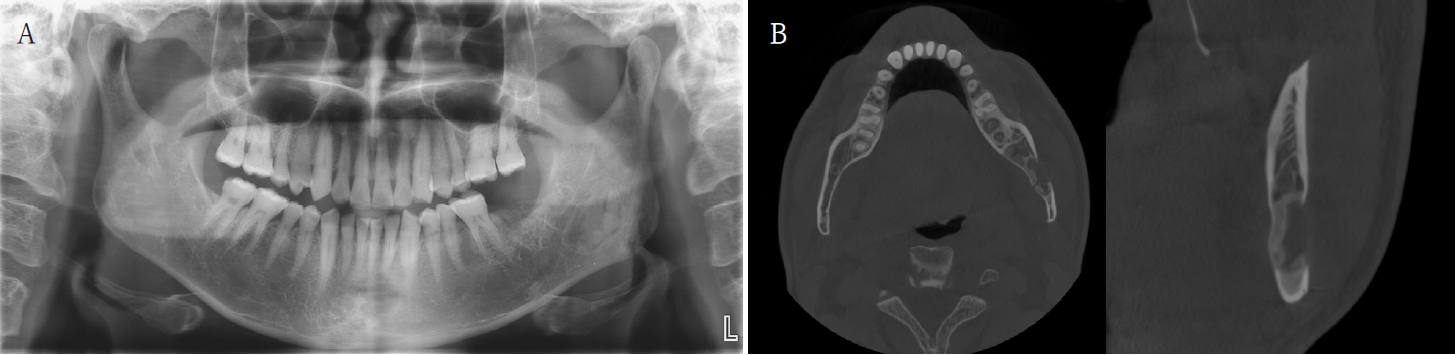

The patient underwent a panoramic radiograph and cone-beam computed tomography (CBCT). The panoramic radiograph showed an ovoid, well-demarcated radiolucency with irregular contour, and internal lytic change beneath the periapical area of the left mandibular third molar region (Fig. 1). CBCT demonstrated a radiolucent lesion with a well-corticated margin and subtle internal calcified foci. Generalized sclerotic changes in the adjacent cancellous bone and thinning of the bucco-lingual cortex were noted, with mild expansion of the lingual cortex due to the lesion (Fig. 2). Anatomically, the lesion lay inferior to the mandibular canal and outside the tooth-bearing alveolus, which argued against an odontogenic origin. Collectively, these features were interpreted as a radiolucent lesion with surrounding sclerosis. Routine laboratory tests (L30 clinical chemistry panel) revealed elevated glucose (135 mg/dL) and total cholesterol (233 mg/dL), while all other parameters were within normal limits. Based on the clinical and radiographic findings-posterior mandibular location, well-defined unilocular radiolucency with a pronounced adjacent sclerotic change, cortical thinning with mild expansion but without periosteal reaction or cortical breach, and non-odontogenic position—the working differential favored non-ossifying fibroma, with a simple bone cyst considered less likely.

Panoramic radiograph shows a radiolucent lesion of irregular shape and relatively well-defined margins beneath the periapical area of the left mandibular third molar.

Axial, parapanoramic, and cross-sectional cone-beam computed tomographic images show a radiolucent lesion with a well-corticated margin and subtle internal calcified foci. Generalized sclerotic changes in the adjacent cancellous bone and thinning of the buccolingual cortex are noted, with mild expansion of the lingual cortex due to the lesion.